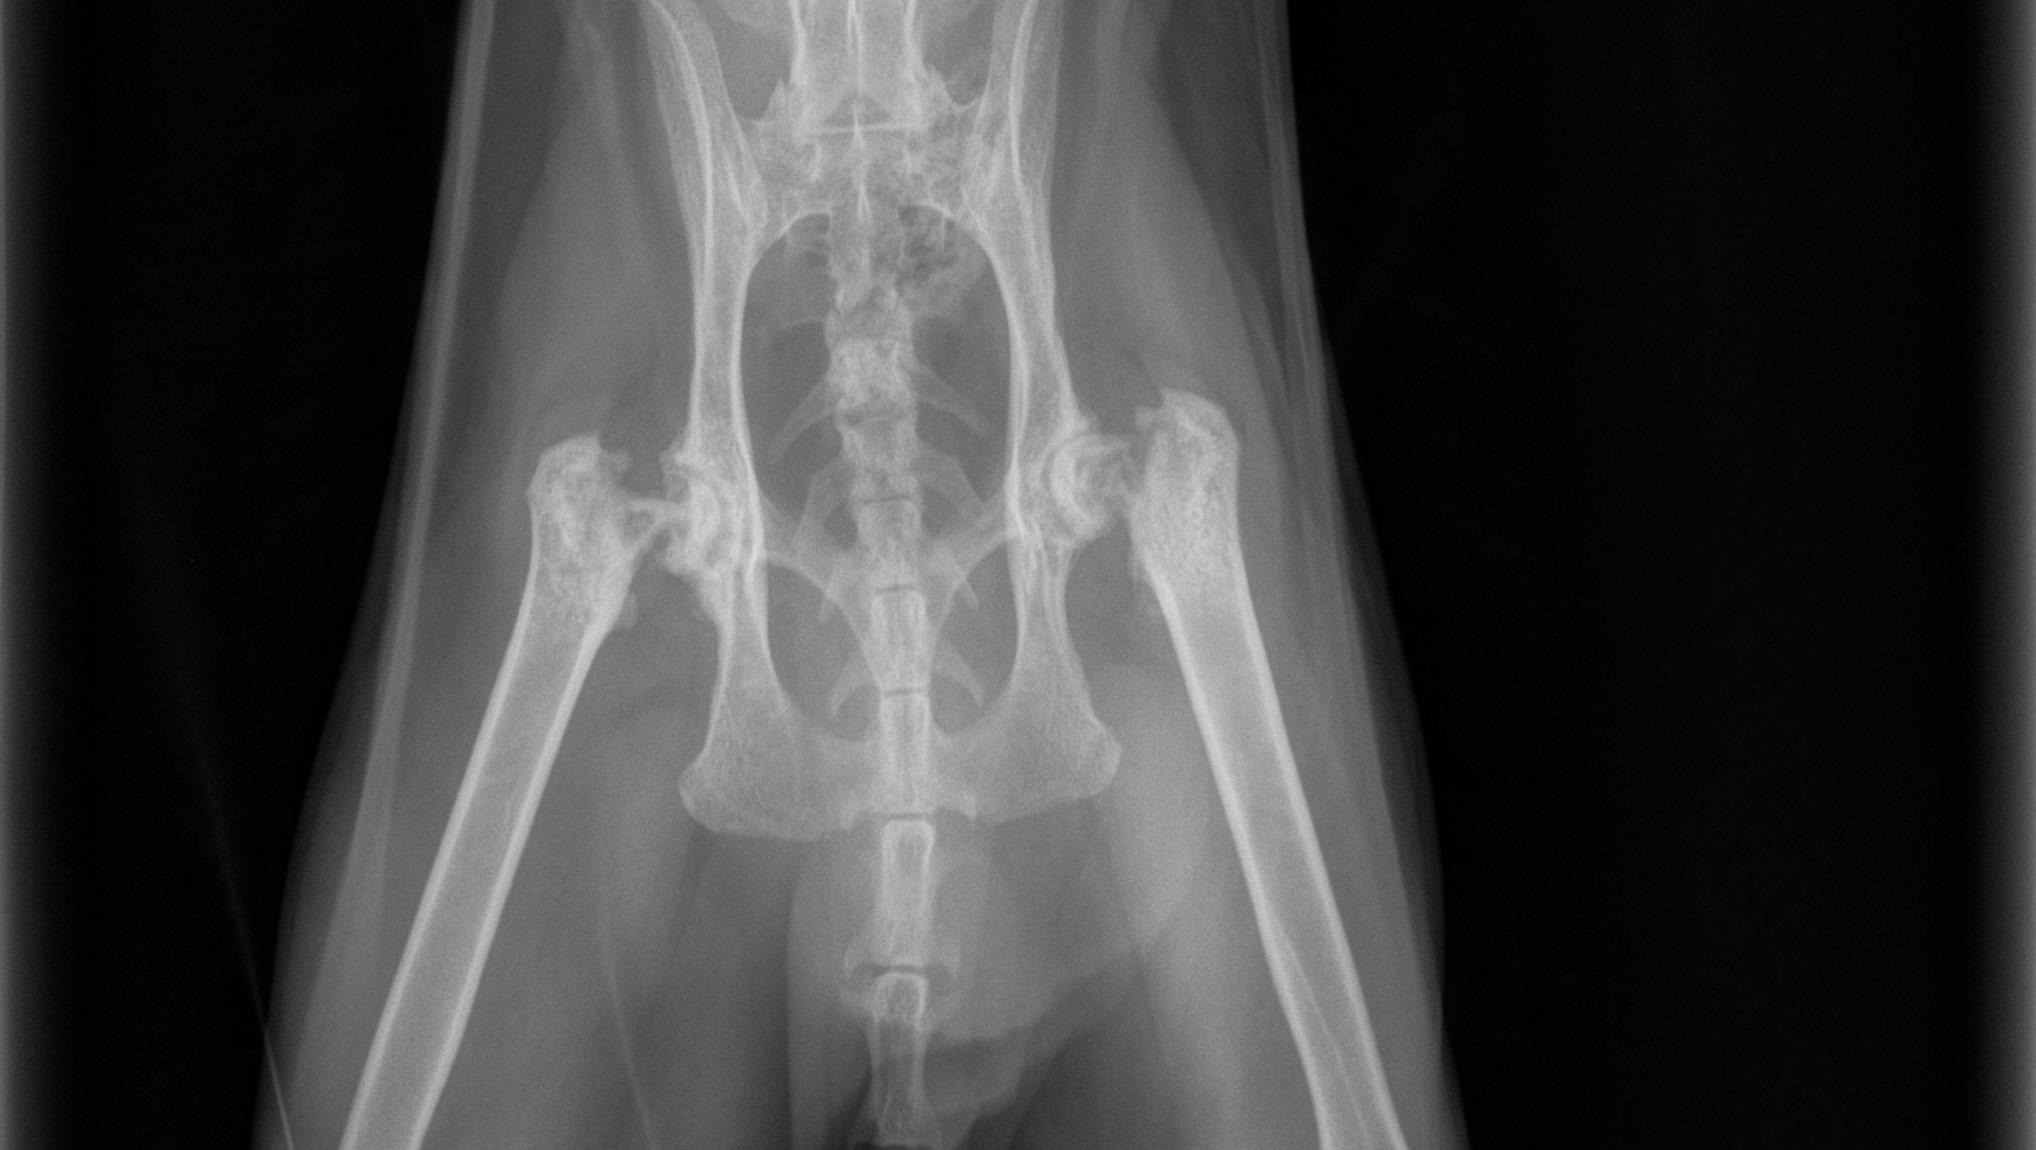

Todd has been very cranky when we go near his hip or butt area, and has stopped jumping and climbing his cat castle. We noticed he started to get skinny turns out his leg muscle was getting weak from not using them. Todd has been diagnosed with femoral neck metaphyseal osteopathy on both legs. This means the ball at the top of his leg that attaches to his hip is disintegrating It is so bad that he has fractures on both femurs or leg balls.This is a very painful condition and will keep spreading further down the femur if it is not fixed.

The treatment is called a femoral head osteotomy. Basically they cut off the ball area that is disintegrated on both sides. Eventually Todd's muscle will grow back in place Todd turns 4 in April and is a young cat the doctors say young cats live a long life if treated with this condition.